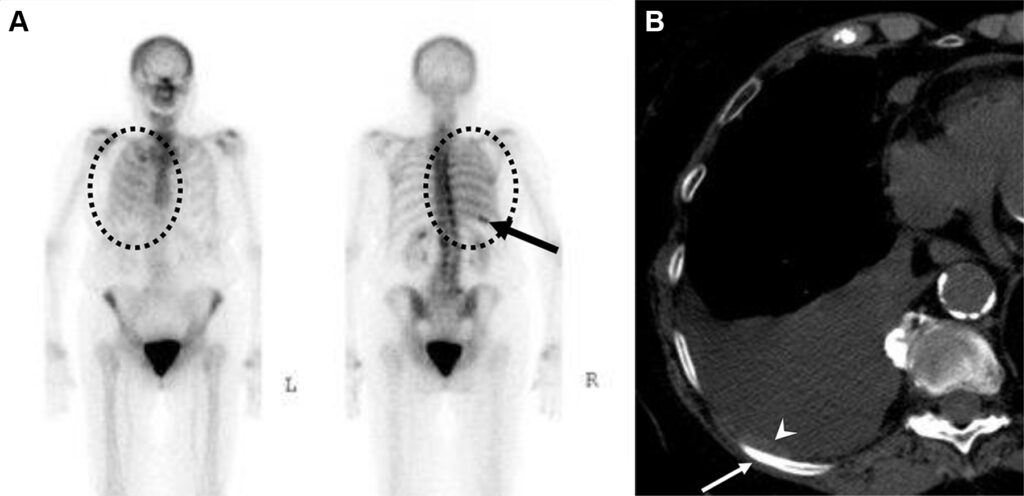

Metastasi costali e pleuriche con versamento pleurico in una donna di 63 anni con tumore al seno.

La scintigrafia ossea con 99mTc-MDP evidenzia una lieve ipercaptazione diffusa che ricalca l’emitorace destro, causata verosimilmente dall’accumulo di tracciante nel liquido pleurico maligno. È inoltre visibile una captazione longitudinale a carico dell’arco posteriore dell’XI costa destra. La TC conferma la natura della captazione, evidenziando il versamento pleurico, un ispessimento pleurico e le iniziali alterazioni osteosclerotiche a carico della costa interessata. Il caso dimostra come la scintigrafia ossea possa rilevare non solo le localizzazioni secondarie scheletriche dirette, ma anche segni indiretti di patologia extra-ossea adiacente (come la captazione pleurica).

Malattia metastatica con pattern miliare in una donna di 44 anni con carcinoma papillare della tiroide.

L’esame total body rileva una tenue ipercaptazione diffusa e simmetrica a livello di entrambi i campi polmonari. Si tratta di una captazione extra-ossea anomala del radiotracciante osteotropo. L’imaging morfologico dell’Rx conferma la presenza di una massiva disseminazione metastatica polmonare, caratterizzata da innumerevoli e minuscoli noduli bilaterali (il classico “pattern miliare”), più addensati alle basi. Il tecnezio difosfonato (99mTc-MDP) può accumularsi in lesioni metastatiche extra-ossee, come quelle polmonari derivanti da alcuni tumori (tra cui il carcinoma tiroideo, mammario o osteosarcoma). Questo fenomeno è spesso dovuto alla presenza di microcalcificazioni all’interno del tessuto neoplastico o ad alterazioni del metabolismo locale del calcio.

Carcinosi peritoneale e ascite in un uomo di 58 anni con carcinoma a cellule renali metastatico.

La scintigrafia ossea total body rileva un’anomala captazione extra-ossea a livello addominale. La distribuzione “a chiazze” (patchy) e diffusa del radiotracciante riflette il suo accumulo all’interno della cavità peritoneale.

L’imaging TC conferma la natura del reperto scintigrafico, documentando la presenza di ascite neoplastica e impianti nodulari solidi (carcinosi) a carico del mesentere e dell’omento.

Analogamente a quanto avviene per i versamenti pleurici, il tecnezio difosfonato può diffondere e accumularsi nei fluidi ascitici o all’interno dei noduli di carcinosi peritoneale. Questo fenomeno secondario è spesso legato all’aumentata permeabilità vascolare locale o alla presenza di microcalcificazioni nel tessuto tumorale.